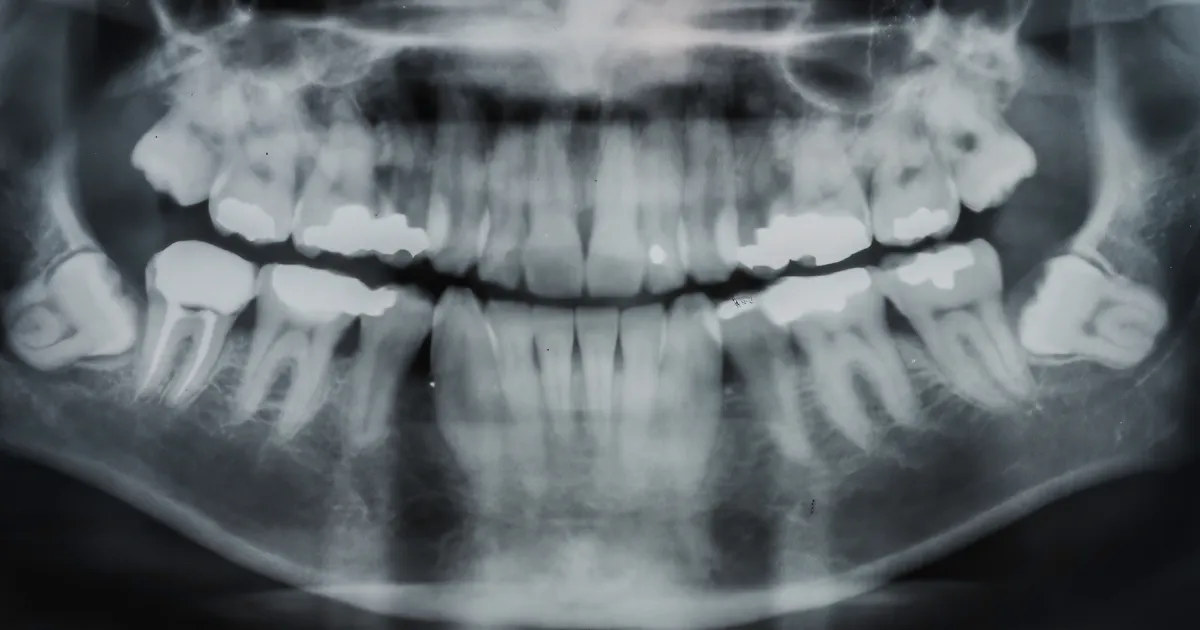

一次拔除四颗智齿的手术方式

如果患者需要一次性拔除四颗智齿,通常使用全身麻醉或静脉麻醉。这样可以保证手术过程中没有疼痛感,同时帮助患者更快恢复。

全身麻醉

全身麻醉下,患者会完全失去意识,适用于需要一次性拔除四颗智齿或手术较为复杂的情况。全身麻醉手术通常需要住院。